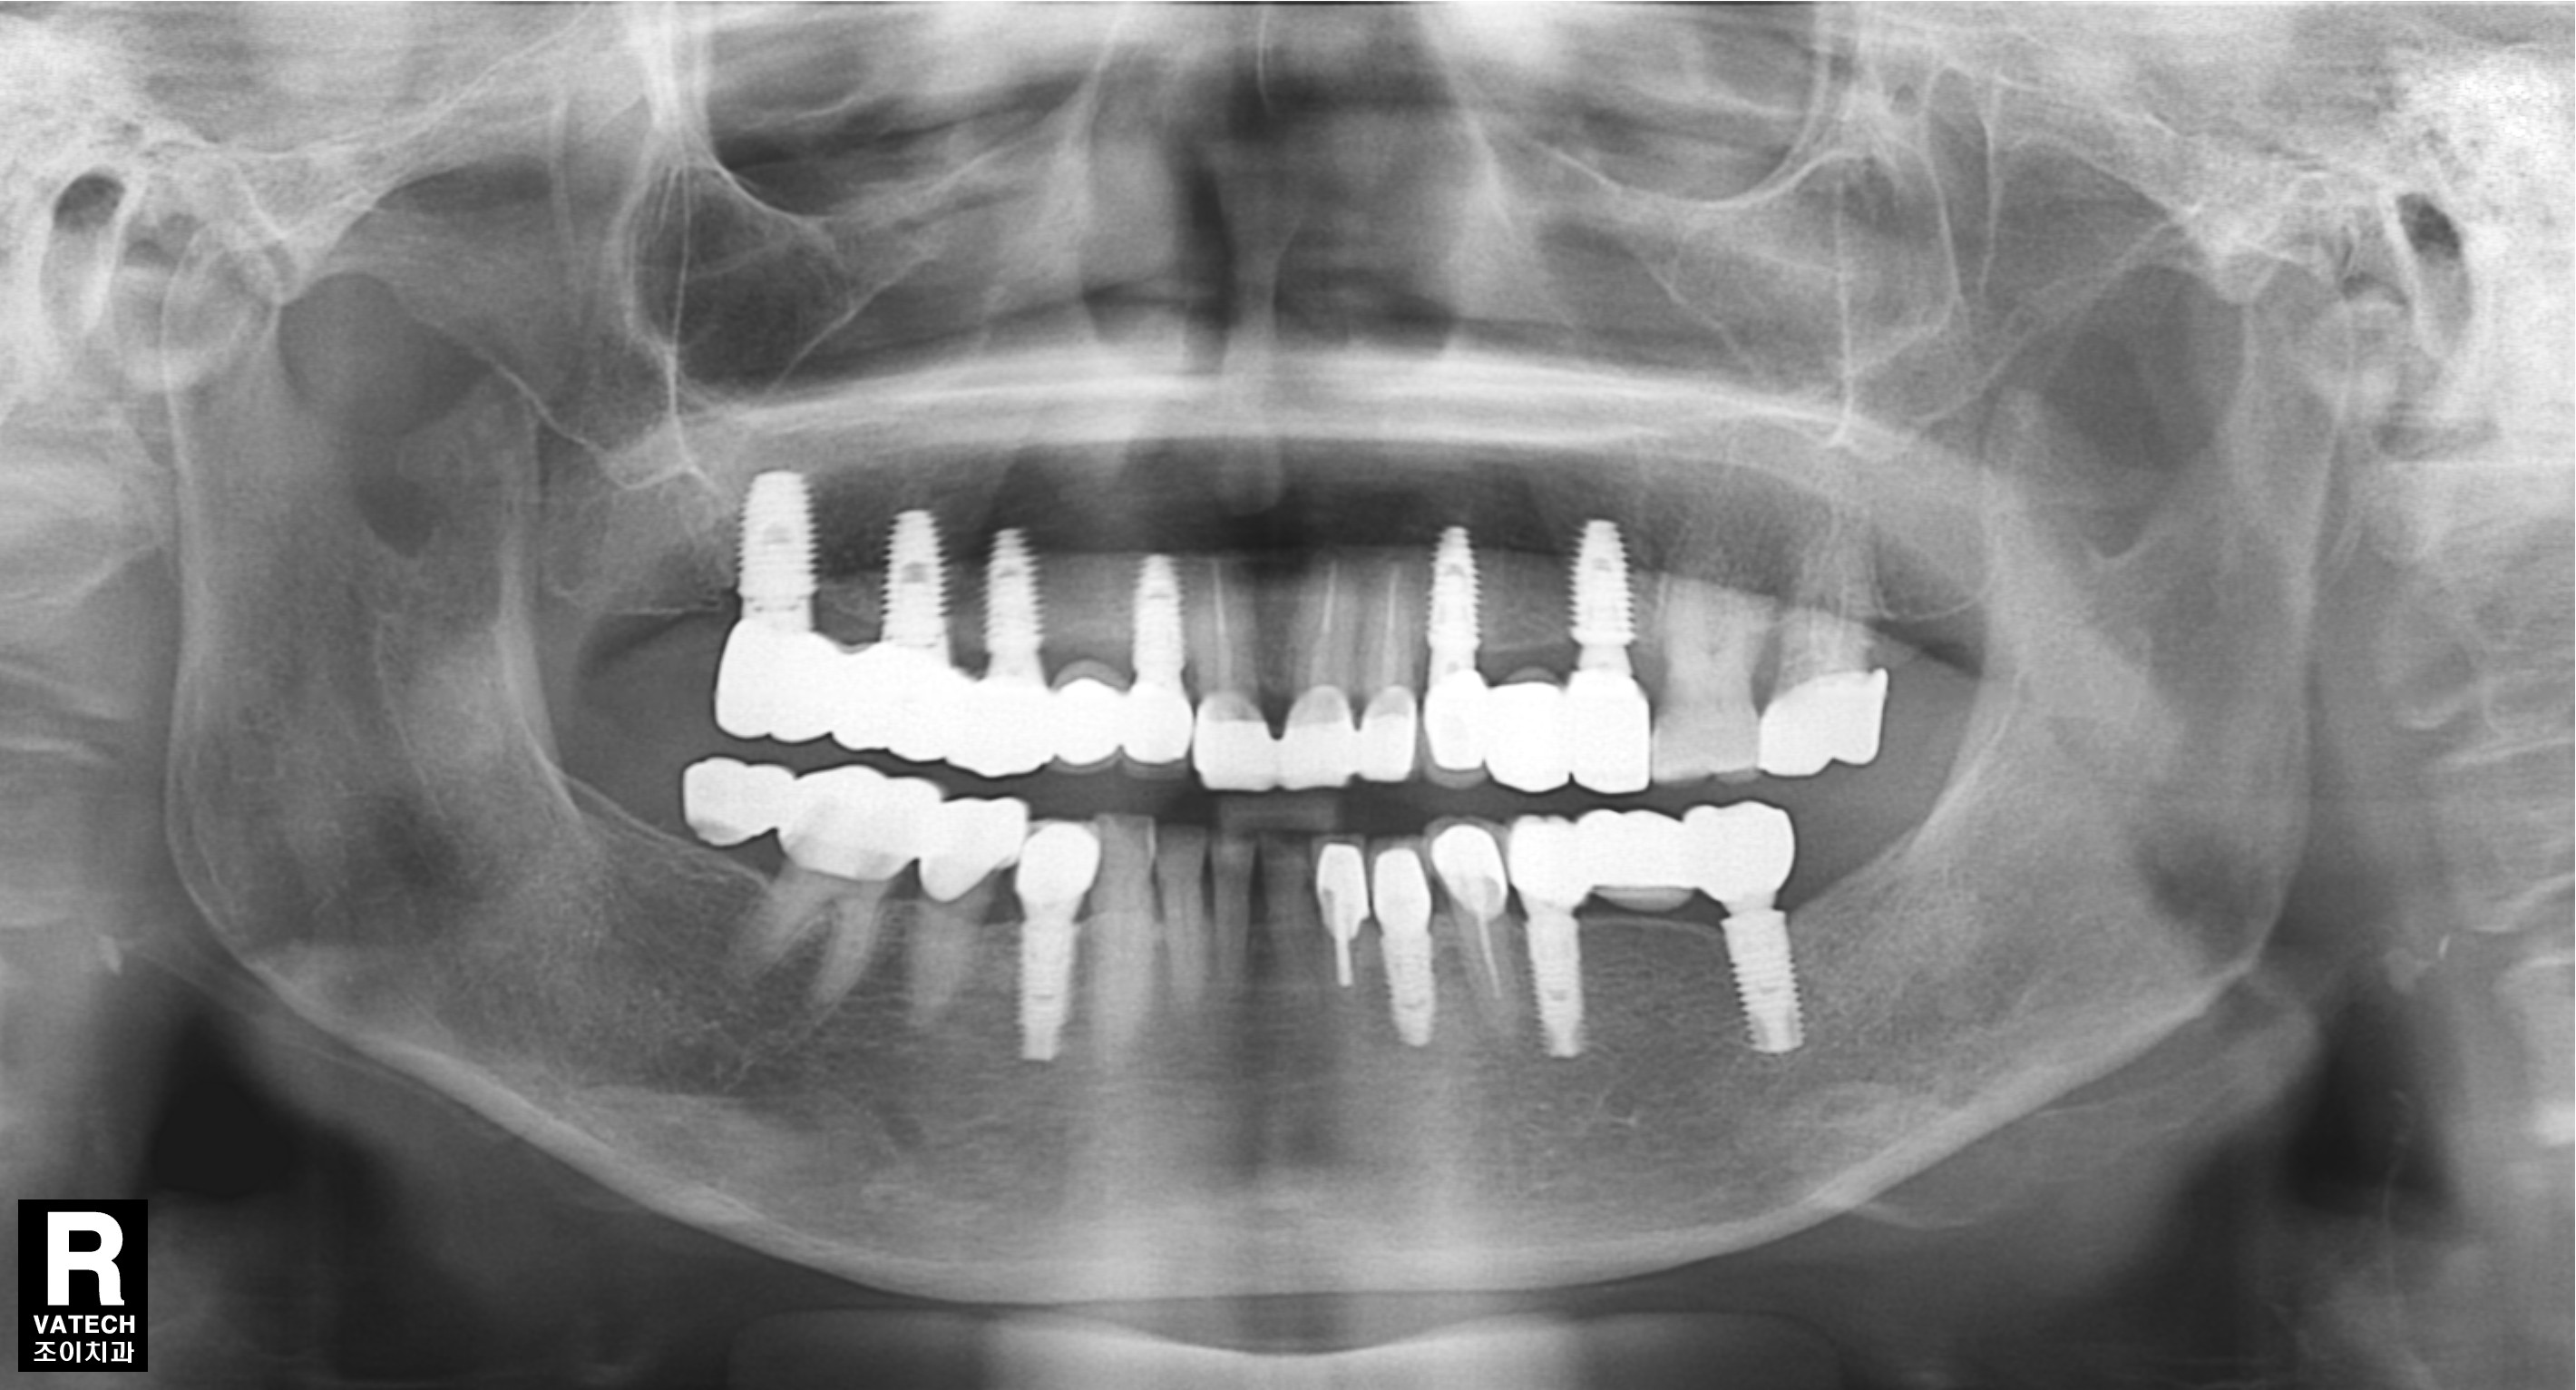

[임플란트] 제목 : 충치로 발치 후

임플란트